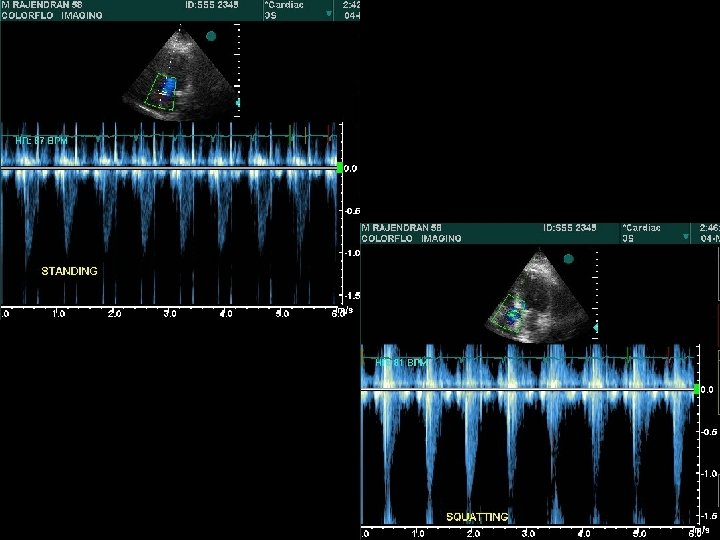

Abrupt standing • S 2 split which may be wide, may narrow down , while the fixed split may persist • A 2 OS interval widens – differentiates from wide split of S 2 • All murmurs ( except MVP/HOCM) decrease • ESM of HOCM becomes louder and longer • Click occurs earlier, murmur becomes longer in MVP – loudness shows variable response

Squatting • Increased venous return and CO > augments most murmurs atleast initially (AS, PS, MR, AR, VSD) Right heart murmurs do so earlier • Increased ventricular volume > murmur of HOCM ↓ murmur of MVP ↓→ • Ejection murmur of TOF ↑

Hemodynamics of Squatting T Murakami AHJ 2002; 15: 986– 988

T Murakami AHJ 2002; 15: 986– 988